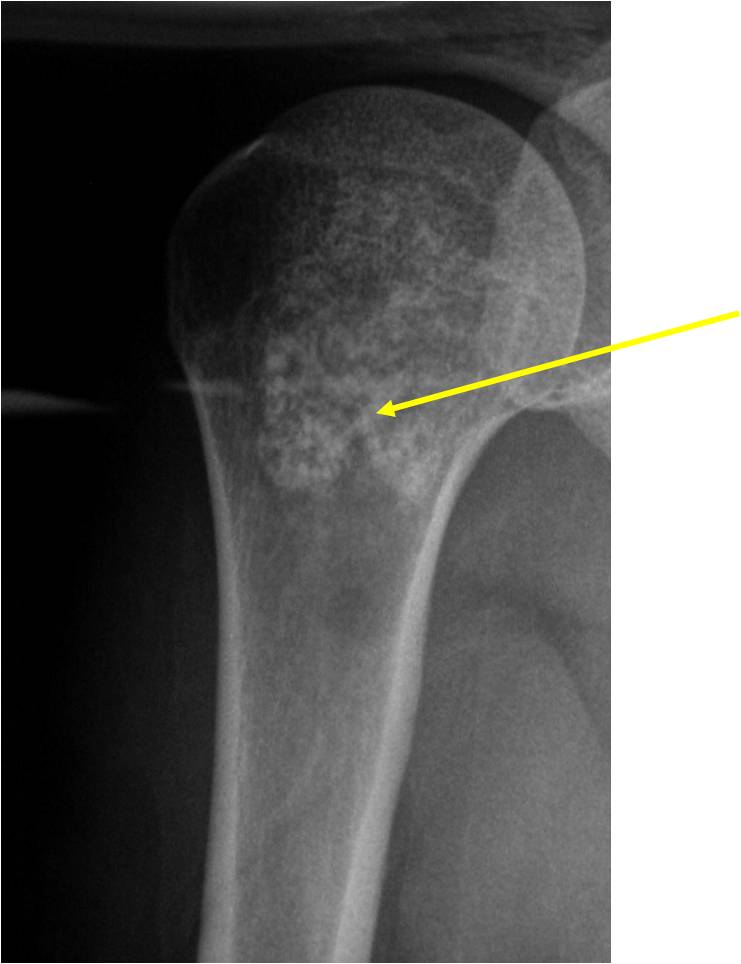

Sites:

- 50% involve hands and feet (mostly phalanges)

- Proximal Humerus, Femur most common long bones

- Most commonly found in metaphysis

Plain X-Ray:

- Geographic lytic lesion

- Central often metaphyseal in long bones

- Expansile remodeling with thinned cortex

- Chondroid matrix with calcifications in majority of tumors

Ring and Arc Calcifications Minimal Endosteal Scalloping Cortex Intact No Soft Tissue Component No Periosteal Reaction

Ring and Arc Calcification No Endosteal Scalloping

Metaphyseal Tumor Heavy Calcifications Ring and Arc Pattern of Calcifications Minimal Endosteal Scalloping No Cortical Destruction No Periosteal Reaction No Cortical Destruction No Soft Tissue Component